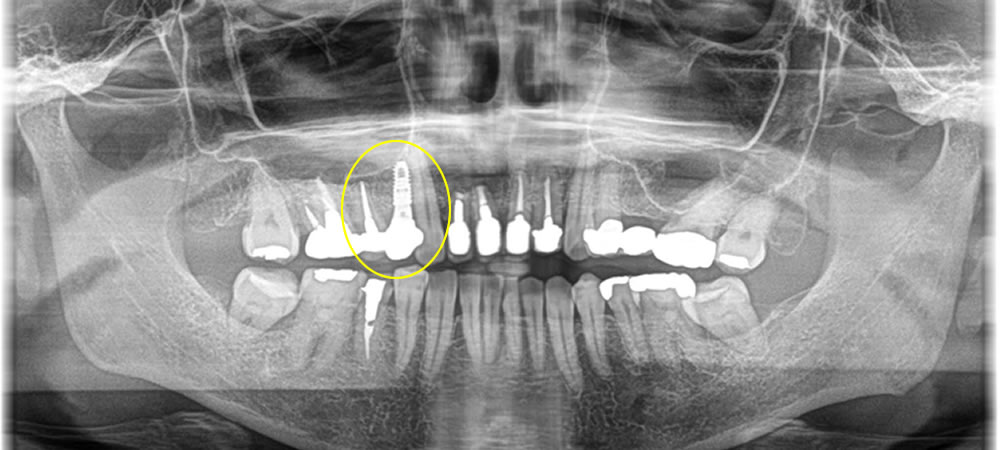

延長ブリッジ部分をインプラントで治療した症例

こちらの患者さまは過去に延長ブリッジを他院にて装着している所にインプラントを希望され来院されました。

骨がしっかりとある事をCTにて確認する事ができたので、今回は切開を7ミリに抑え低侵襲でオペを行いました。

この方法により術後の痛み、腫れを最小限に抑える事ができました。縫合も行わずにすんだので糸を取る処置も必要ありません。